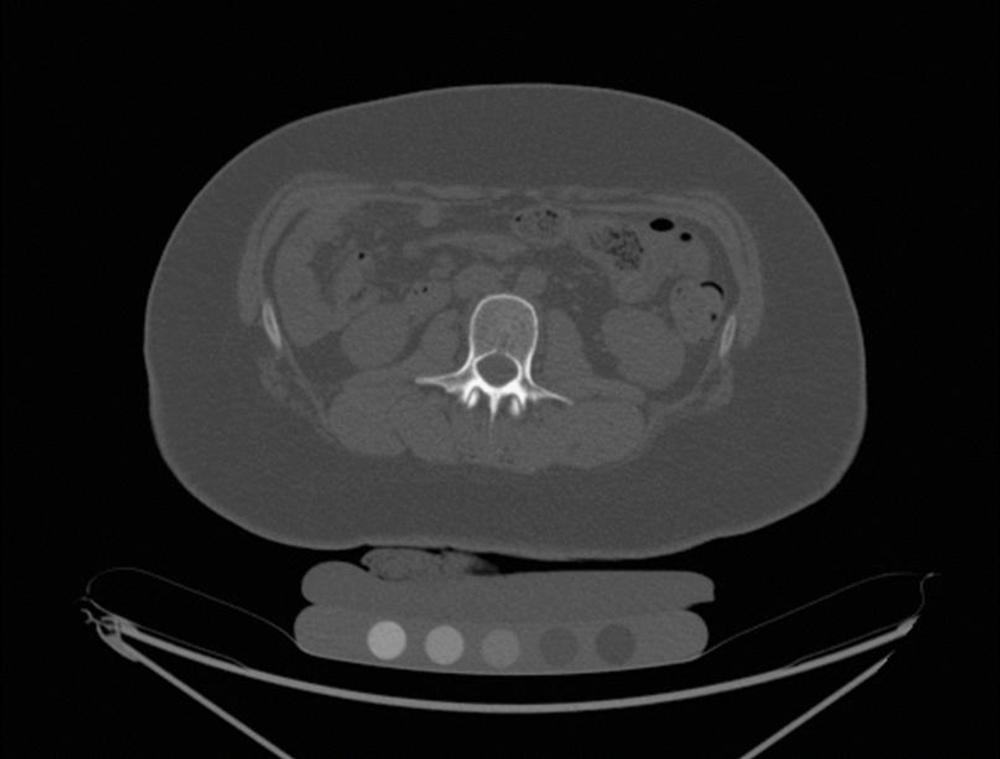

Figure 2. Children lost bone mineral density one year after sleeve gastrectomy. CT in a 17-year-old female one year after surgery. Volumetric bone mineral density post-surgery was 146 mg/cm3 from 183 mg/cm3.

High-res (TIF) version